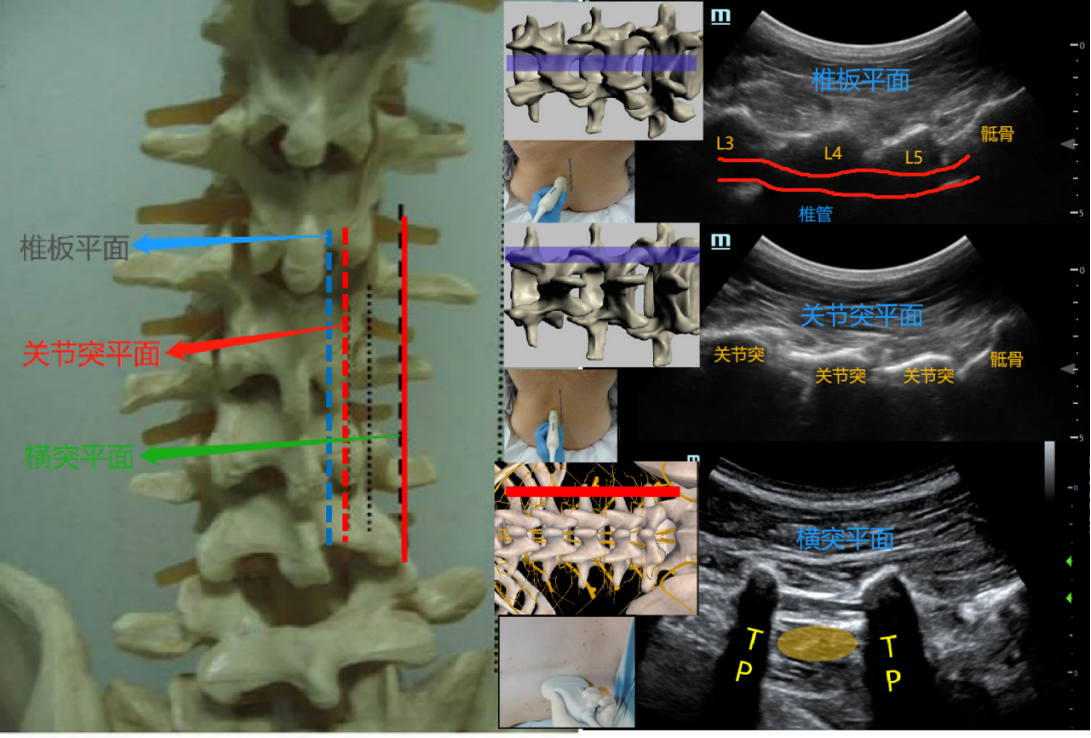

脊柱旁正中矢状面:该切面临床上最常用,相对简单。根据探头在腰椎不同解剖部位,分为椎板矢状面、关节突矢状面、横突矢状面。其中横突矢状面临床最常用。